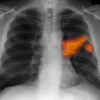

Kanser Ölümlerinde Akciğer Birinci Sırada

Dünya Sağlık Örgütü'nün 2015 yılı Şubat ayında yayınladığı verilere göre, dünyada 8 milyon 200 bin olan kanser ölümlerinde 1 milyon 590 bin vakayla akciğer kanseri ilk sırayı aldı Akciğer kanserini karaciğer, mide, kalın bağırsak, meme ve yemek borusu kanserleri izledi Kanserden ölümlerin üçte birine neden olarak yüksek beden kitle indeksi, yetersiz meyve sebze tüketimi, fiziksel aktivite yetersizliği, alkol ve tütün kullanımı gösterildi.

EFSUN YILMAZ - Dünya Sağlık Örgütü'nün (DSÖ) 2015 yılı Şubat ayında yayınladığı verilere göre, dünyada 8 milyon 200 bin olan kanser ölümlerinde 1 milyon 590 bin vakayla akciğer kanseri ilk sırayı aldı.  DSÖ'nün resmi internet sitesinde yayınlanan verilerden AA muhabirinin derlediği bilgilere göre, 2012 yılında da kanser vakaları en büyük hastalık ve ölüm nedenleri arasında yer aldı.  Dünyada 14 milyon yeni kanser vakasına rastlanırken, 8 milyon 200 bin ölümün de kanserden kaynaklandığı belirlendi.  Erkekler arasında en sık rastlanan 5 kanser türü akciğer, prostat, kalın bağırsak, mide ve karaciğer türleri olurken, kadınlarda ise en sık olarak sırasıyla meme, kalın bağırsak, akciğer, rahim ağzı ve mide kanserleri görüldü.  Üçte birinin nedeni davranış ve beslenme  Rapora göre, kanserden ölümlerin üçte 1'ine yüksek beden kitle indeksi, yetersiz sebze ve meyve tüketimi, fiziksel aktivite eksikliği, tütün ve alkol kullanımı gibi davranmış ve beslenme sorunları gösterildi.  Tütün kullanımı en büyük risk faktörü olarak belirlenirken, tüm kanser türlerinden ölümlerin yüzde 20'sine, akciğer kanserlerinden ölümlerin ise yüzde 70'ine sebep oldu.  Kanser sebebi Hepatit B gibi viral enfeksiyonlar da düşük ve orta gelirli ülkelerdeki kanser ölümlerinin yüzde 20'sine neden olarak gösterildi.  Akciğer kanseri ilk sırada Yeni kanser vakalarının yüzde 60'ından fazlası Afrika, Asya, Orta ve Güney Amerika'da görüldü. Bu bölgelerde kanserden ölüm oranı ise lerin yüzde 70. Genel kanser ölümlerinde de 1 milyon 590 bin ölümle akciğer kanseri ilk sırada yer aldı. Akciğer kanserini 745 bin ölüm sayısıyla karaciğer, 723 bin ölüm sayısıyla mide, 694 bin ölüm sayısıyla kalın bağırsak, 521 bin ölüm sayısıyla meme, 400 bin ölüm sayısıyla da yemek borusu kanserleri izledi.  Yıllık 14 milyon olan kanser vakalarının 20 yıl içinde 22 milyona yükseleceği tahmin ediliyor. - İzmir